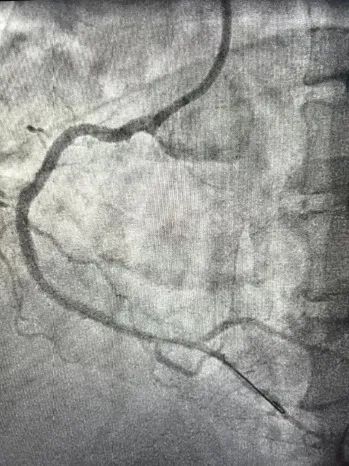

患者男性,63岁,既往糖尿病肾病,慢性肾功能不全规律血液透析,RCA曾行PCI。本次因为心力衰竭入院,入院后超声提示左室EF 仅有24%,伴有中量二尖瓣反流,冠状动脉造影提示:右优势型,血管走行区可见重度钙化影,LAD 中段次全闭塞,LCX近端重度狭窄;RCA支架内再狭窄,支架近端及远端均存在重度狭窄。患者拒绝CABG,遂在IABP的支持下,首先处理LAD。本次择期处理RCA病变,由于RCA近端血管钙化迂曲,IVUS探头无法通过,遂在延伸导管的支持下,直接进行Shockwave IVL(3.5mmX12mm)治疗,在经过8个周期80个脉冲对RCA多处靶病变进行充分预处理后,以药物洗脱支架联合药物洗脱球囊的方式顺利完成RCA的血运重建。目前患者EF由24%上升至43%,心衰症状明显缓解。

图1:冠状动脉造影提示RCA弥漫钙化伴多处重度狭窄